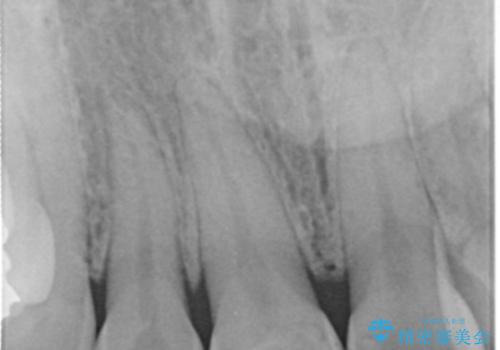

- 上顎前歯の歯冠部が破折した患者様です。神経にまでは到達していなかったので精密根管治療は行わず、審美性を考慮し、オールセラミッククラウンでの治療を選択しました。

歯ぎしりのある患者様なので、就寝時にマウスピースを着用するようにお伝えしています。

- かみ合わせや歯ぎしりが強すぎる方はセラミックが割れてしまう可能性があります